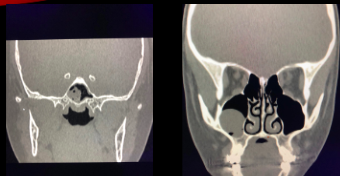

19

Q

¿Qué se ve en esta imagen?

A

Calcificaciones por Aspergillus